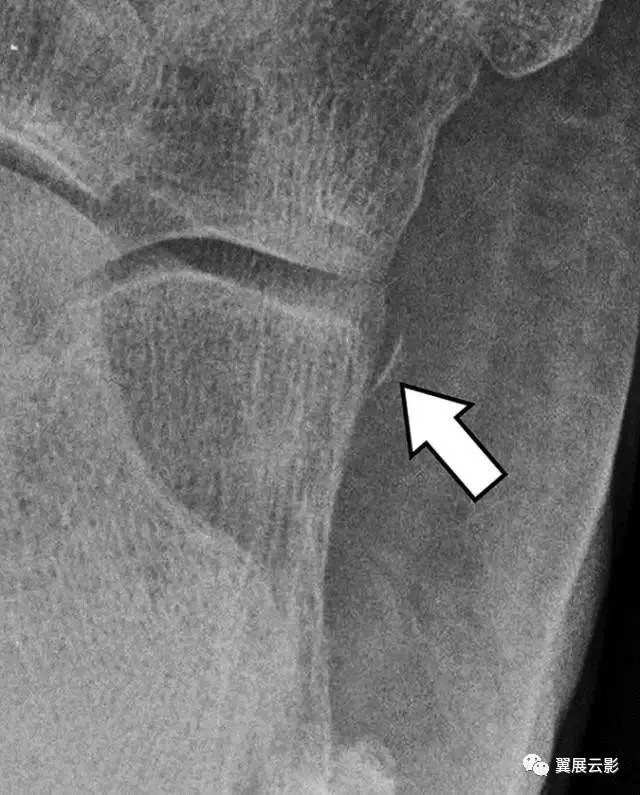

导致前跟骨前部断裂的两种损伤机制是压缩或撞击力和极端拉力[29]。压迫性骨折的发生是由于在外翻和背屈的过程中,来自骰骨和距骨前方(称为“胡桃夹子”病变)的撞击,或者前脚掌被固定在地面上的有力外展[30,31] 。撕裂性骨折是由于在脚的强力反转和足底屈曲期间在分叉韧带上的张力引起的。事实上,这种骨折构成了影响跟骨的最常见的撕脱骨折[26]。一般来说,嵌塞性骨折大于撕裂性骨折。这些骨折是重要的,因为它们与其他足异常有很强的关联,例如前踝韧带断裂,其他跗骨骨折以及腓神经腱的损伤[29,32]。踝的侧位放射线照片提供了骨折的识别,其特征在于通过该过程垂直地出现骨折线(图7)。如果侧位片是可疑的,脚需拍摄斜位片用以诊断[24]。前路骨折分为三种类型:1型骨折小(<1厘米)和无错位,2型骨折具有最小(> 2毫米)位移,并且没有涉及跟骨神经节关节,3型骨折被粉碎或大型, 跟骰关节受累(> 25%)[31]。

图7A-25岁的男子在滑雪时跌倒。侧位片显示跟骨骨折应于2型骨折(箭头)。

图 7B - 脚的斜位片识别骨折(箭头)。